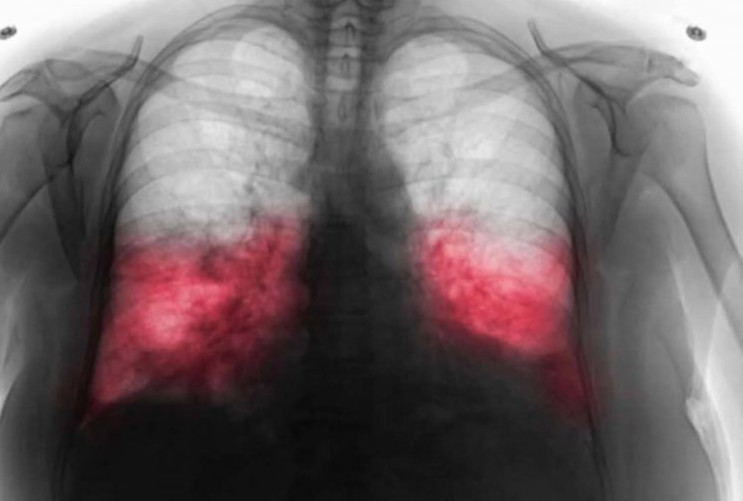

Kada pacijent posjeti ljekara sa sumnjom na hodajuću upalu pluća, obično se provodi dijagnostički pregled. To može uključivati laboratorijske testove i rendgenski snimak pluća kako bi se utvrdilo prisustvo infekcije. U nekim slučajevima, doktor može uzeti bris iz dišnih puteva kako bi precizno identifikovao uzročnika. Također, važan dio dijagnostičkog procesa su i anamneza i fizički pregled, koji pomažu u utvrđivanju ozbiljnosti simptoma.